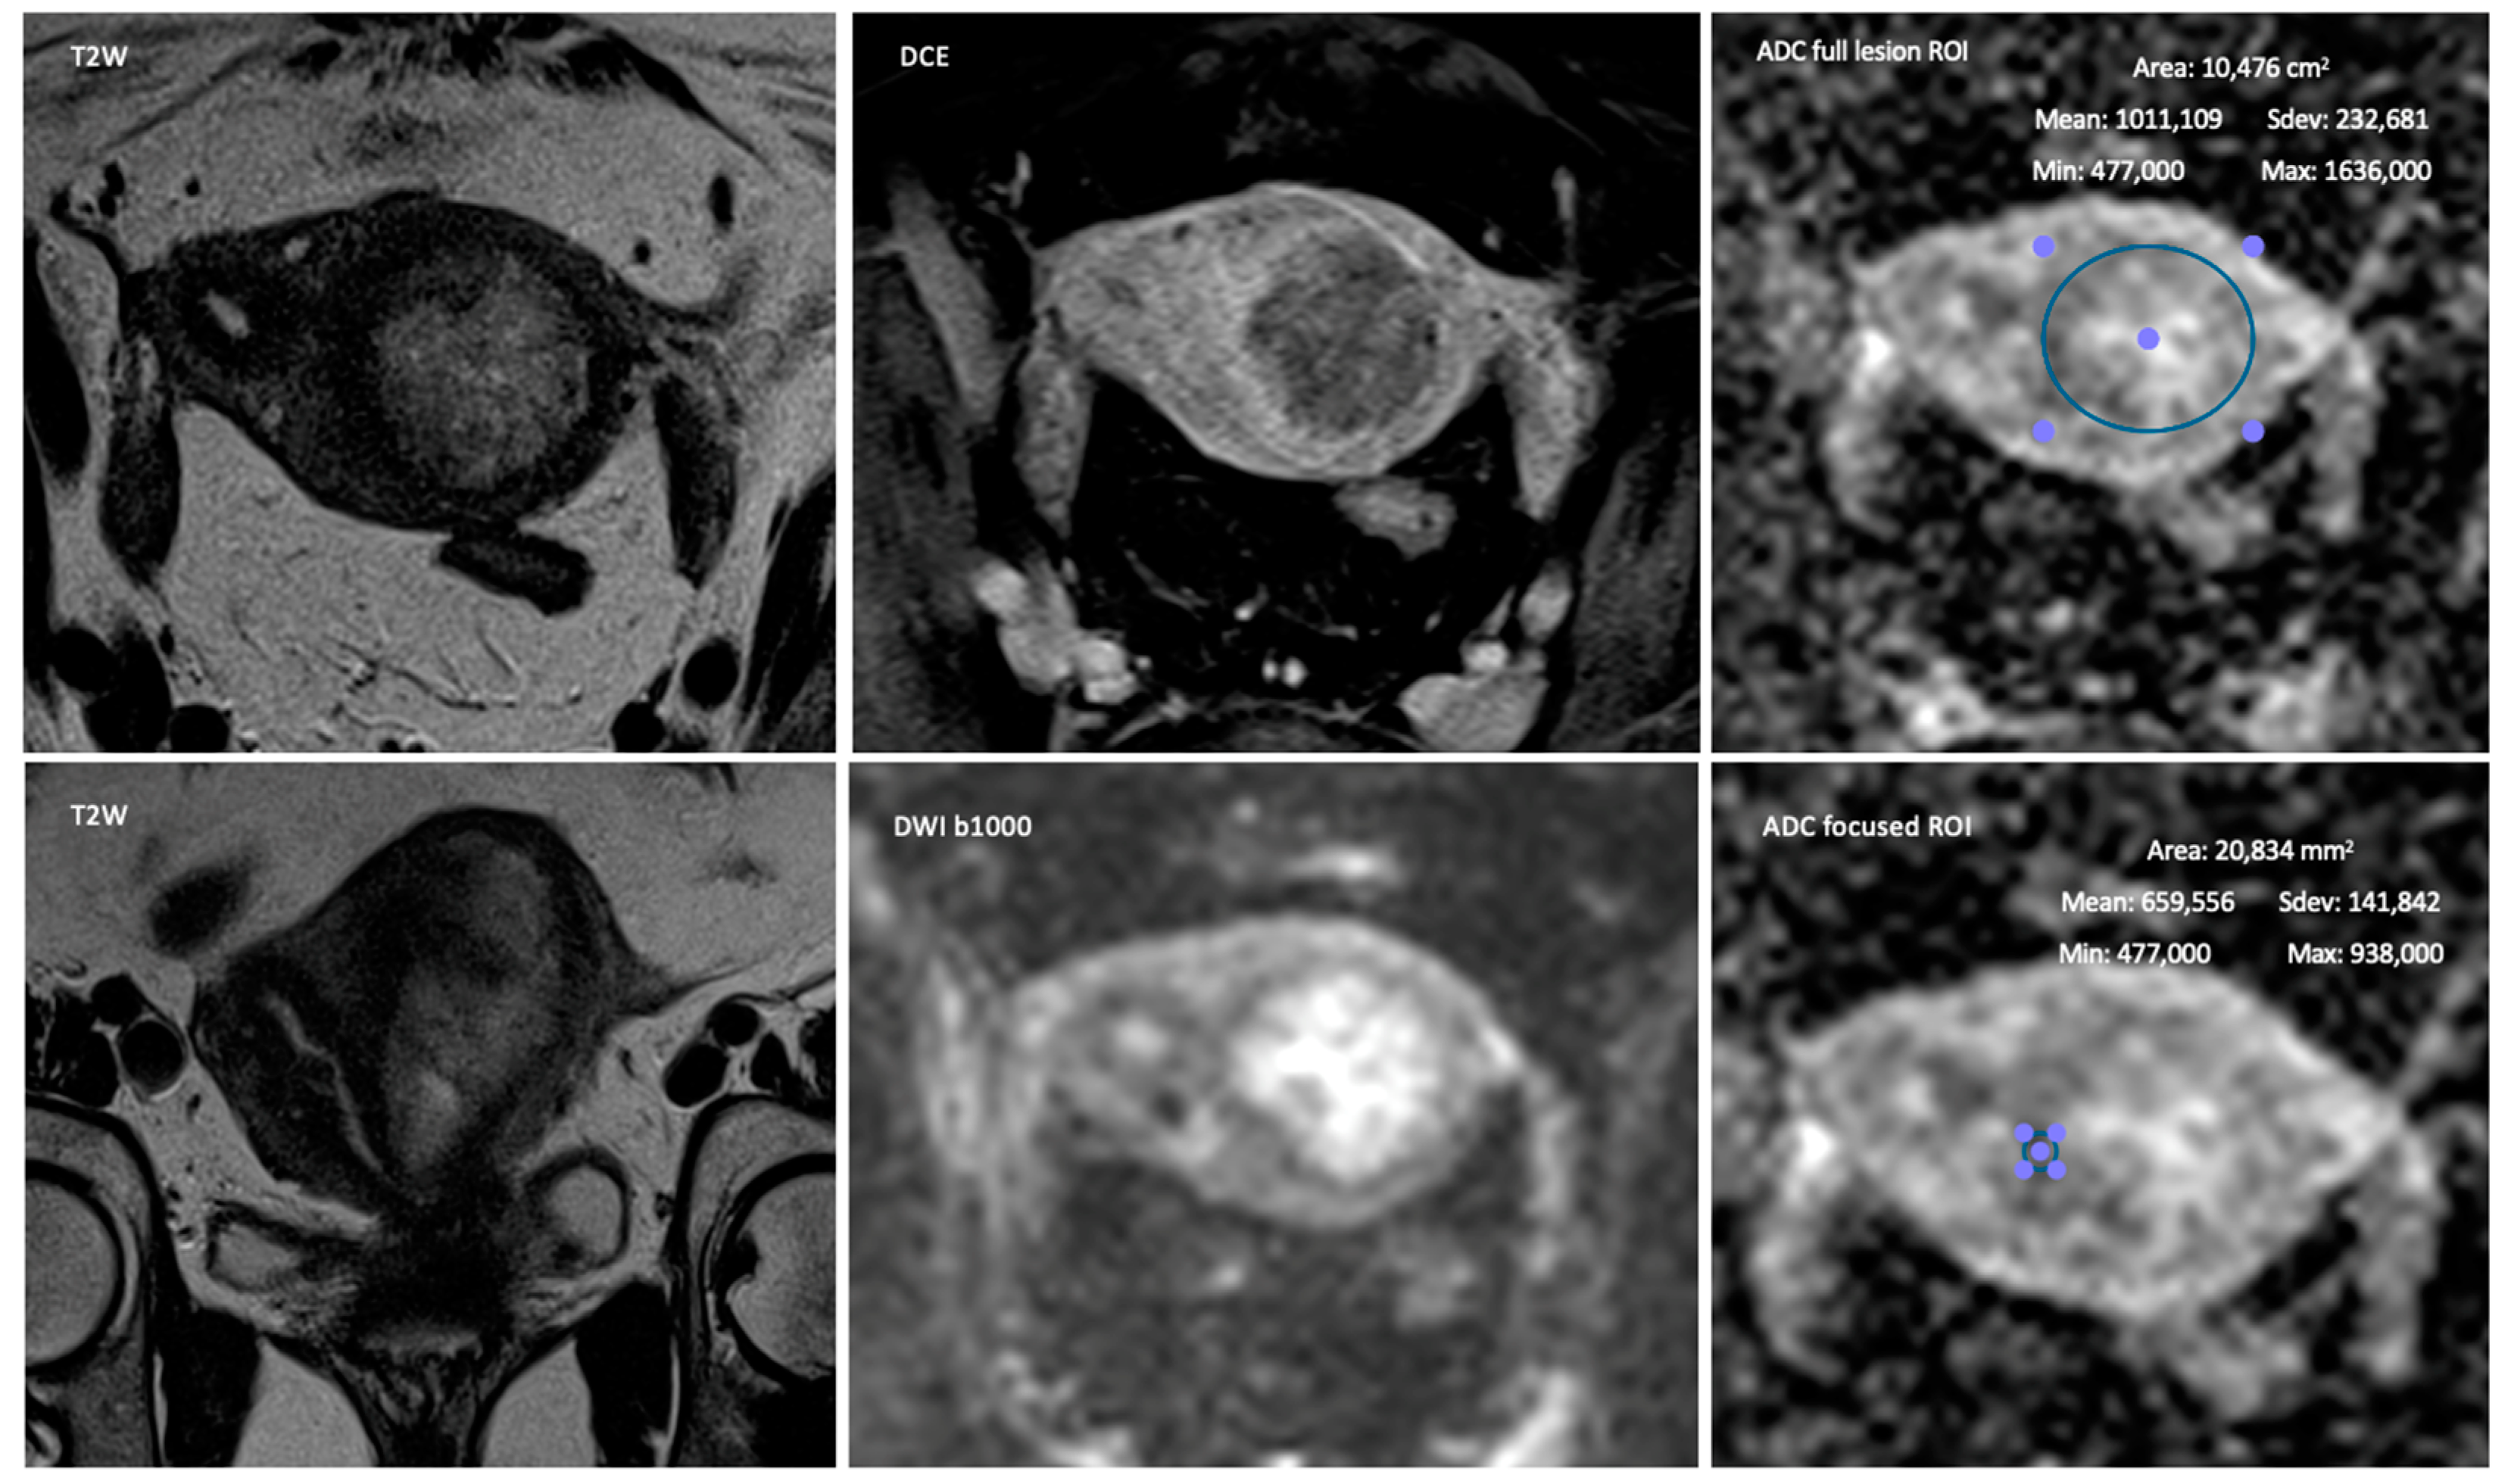

1. Introduction

2. Materials and Methods

2.2. MR Imaging

2.3. Image Interpretation